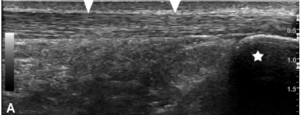

..to looking like this:

or like this….